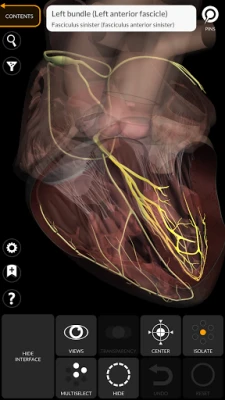

• Cardiovascular system

• Simple and intuitive interface

• Rotate and zoom each model in 3D space

• Option to hide or isolate single or multiple selected models

• Transparency function

• By selecting a model or a pin, the related anatomical term shows up

• The anatomical terms and the user interface are available in 11 languages: Latin, English, French, German, Italian, Portuguese, Turkish, Russian, Spanish, Chinese, Japanese and Korean

• The anatomical terms can be displayed in two languages simultaneously